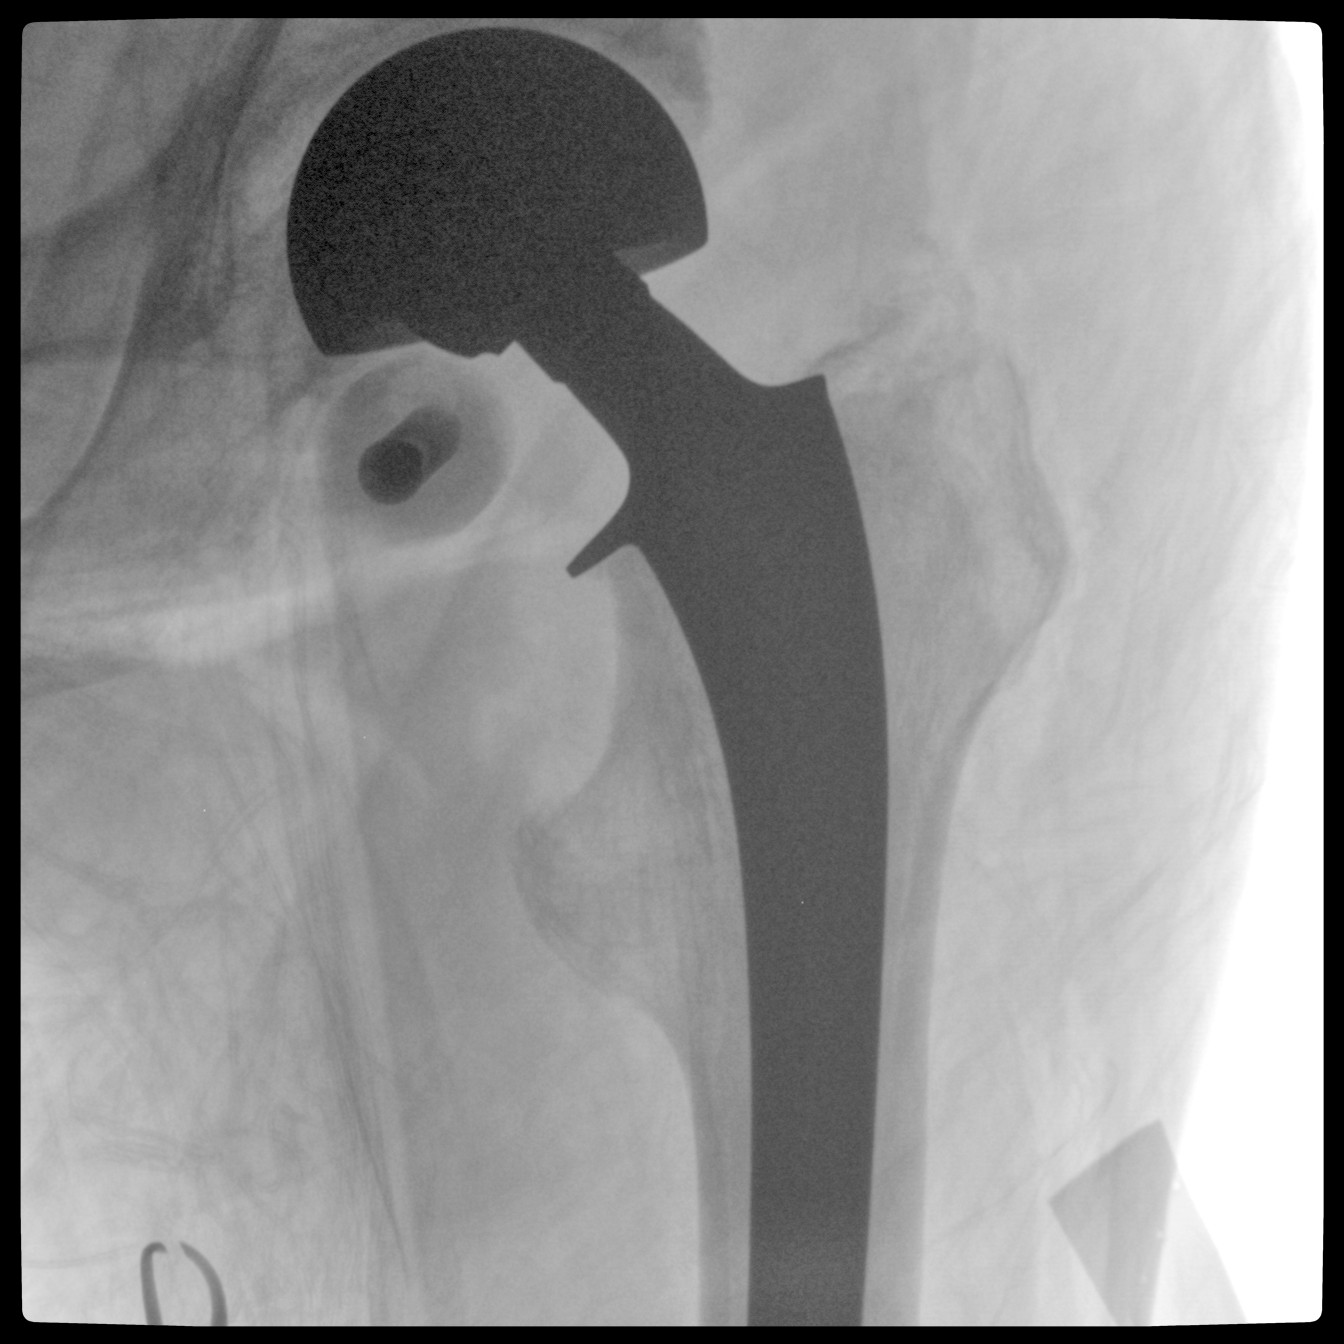

配備了兩種平板尺寸,大尺寸動態(tài)平板探測器成像面積較傳統(tǒng)平板探測器提升了25%以上,在視野需求大的手術中,便于醫(yī)生更好定位病灶點,規(guī)劃手術方案,減少因視野范圍不足而多次透視、點片造成的不便。

Clinical picture

臨床圖片